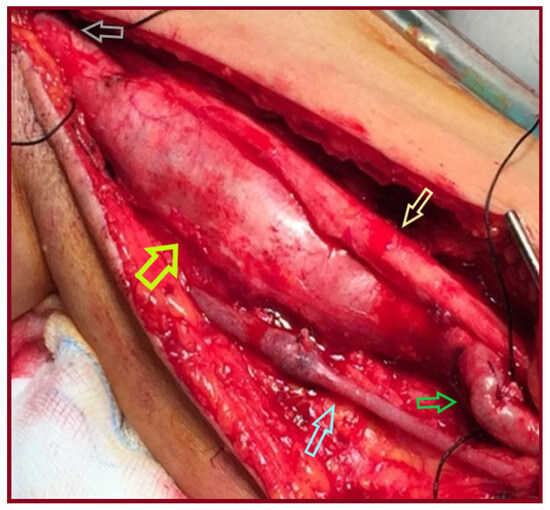

Idiopathic True Aneurysms of the Brachial Artery: A Short Case Series and Scoping Review

Background: Brachial artery aneurysms are a rare entity occurring sporadically at all ages. Common causes are trauma, infection, connective tissue disorders, genetic syndromes, immunosuppression, and a history of arteriovenous vascular access. Pseudoaneurysms are mainly of traumatic or iatrogenic origin. Idiopathic true brachial artery [...] Read more.

Background: Brachial artery aneurysms are a rare entity occurring sporadically at all ages. Common causes are trauma, infection, connective tissue disorders, genetic syndromes, immunosuppression, and a history of arteriovenous vascular access. Pseudoaneurysms are mainly of traumatic or iatrogenic origin. Idiopathic true brachial artery aneurysms are even scarcer, attributed to inherited susceptibility for aneurysm formation or to atherosclerosis. Due to the rarity of these aneurysms, we report our experience along with a current literature review. Methods: A retrospective search was conducted in the Vascular Surgery Department database of a tertiary referral center for vascular surgery, covering procedures from January 1991 to October 2025. Patients were included if they had undergone idiopathic true brachial artery aneurysm repair. Clinical records, operative details, imaging studies, and follow-up data were reviewed. We additionally provide a literature review regarding clinical presentation, signs, pathophysiology, diagnosis, and treatment of these aneurysms. Results: Amongst all procedures performed for aneurysmal repair, in the searched period, we identified three patients who met these criteria. All three underwent successful elective operations. Individual characteristics of the retrieved cases are reported. Conclusions: The open repair of true idiopathic brachial artery aneurysms is a technically simple approach that leads to satisfactory outcomes. Endovascular therapy is technically unfavorable in this type of aneurysm. Full article

Show Figures

Figure 1